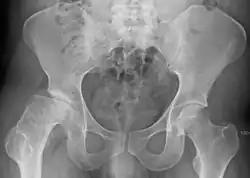

Radiograph of a person with Legg–Calvé–Perthes disease | |